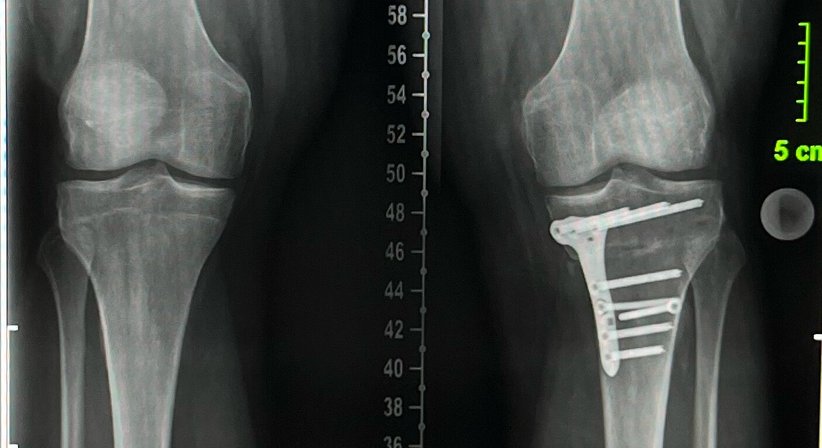

Osteotomie - Beinachsenkorrektur

Am Kniegelenk führen sowohl eine X- als auch eine O-Bein Stellung zu Beschwerden.

Nach genauer Analyse der Fehlstellung kann diese sowohl am Oberschenkel und/oder am Unterschenkel korrigiert werden um eine fortschreitende Arthrose (Gelenkabnutzung) zu bremsen oder starke Beschwerden zu bessern.